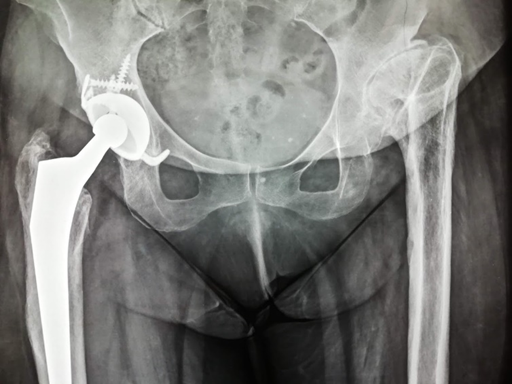

Ασθενής 34 ετών μετά από τραυματική επιφυσιολίσθηση σε ηλικία 11 ετών με αποτυχημένη αντιμετώπιση

Γυναίκα 30 ετών με υποκεφαλικό κάταγμα τον τελευταίο μήνα της κύησης αντιμετωπίσθηκε αρχικά με ήλωση που απέτυχε

Γυναίκα 45 ετών με αμφοτερόπλευρη αναπτυξιακή δυσπλασία (ΣΕΙ)